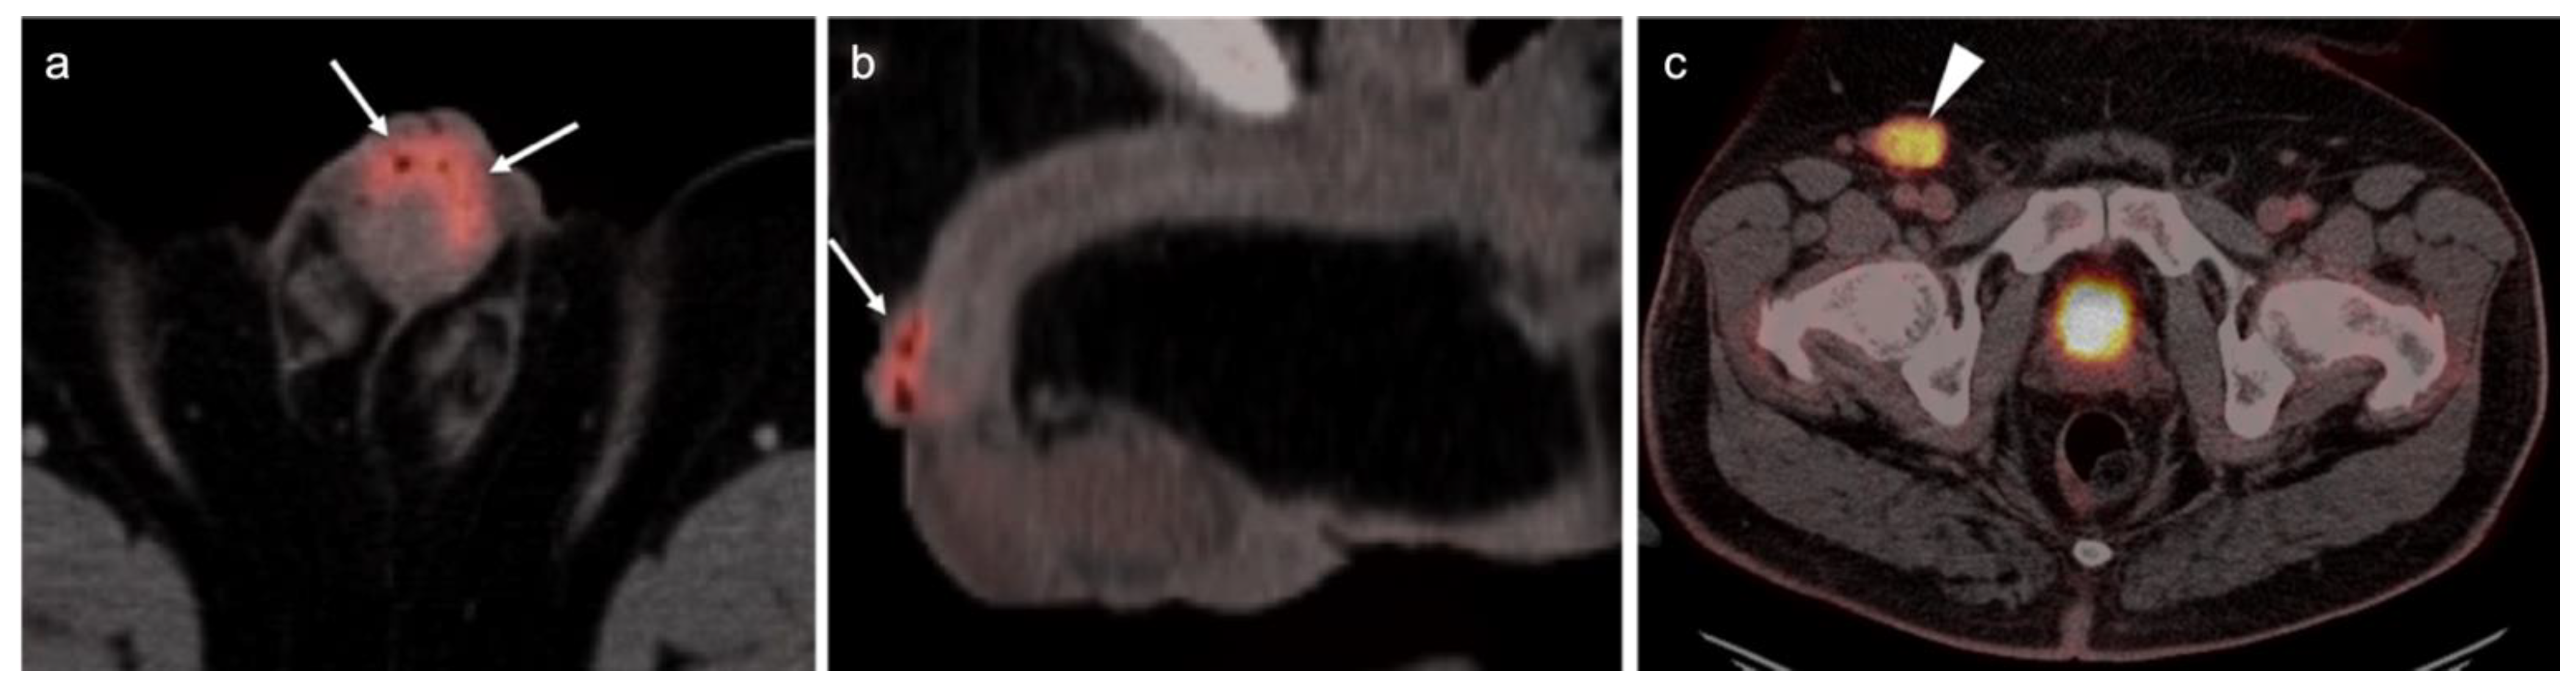

Abstract

2.6. Vulvar Carcinoma

2.7. Considerations of Pregnancy

3.3. Primary Testicular Cancer